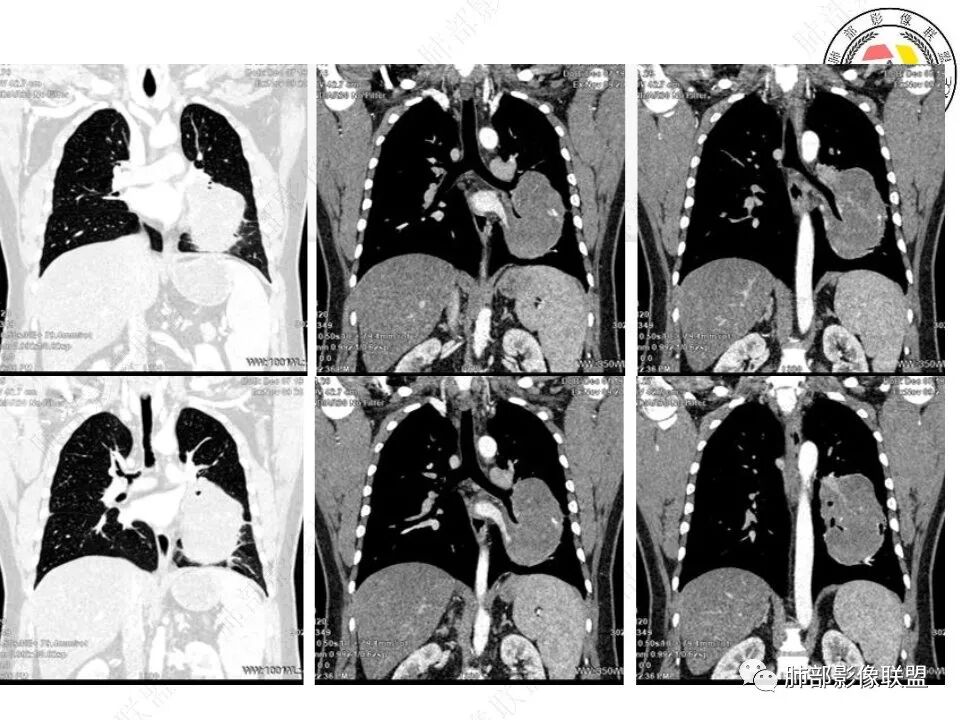

我将内部结构再重建一下

骑跨在斜裂上

局部斜裂稍增厚

下叶基底干支气管受压下移

下叶背段支气管受压稍后内移位,通畅

就是支气管目前基本没有堵塞,只是受压

下肺静脉:

还是肺动脉供血,肺静脉引流

空气新月征:

新月征很有特点,血管有特点

青年男性,体检发现左肺不规则类圆形占位性病变,叶间裂区域,定位胸膜来源。左肺下叶支气管受压狭窄,但管壁光整,未见腔内阻塞或管壁受侵。包块边界清晰,浅分叶,内部密度不均匀,病灶后份见空气新月征。渐进性强化,增强动脉期见分支状血管,蛇纹血管征。肺门纵膈未见增大淋巴结,符合孤立性纤维瘤(SFT)。